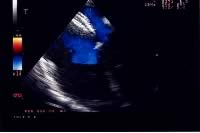

La procedura di impianto viene eseguita in anestesia generale con intubazione del paziente. Un ruolo essenziale, in tutte le fasi della procedura, è svolto dall’ecocardiografia transesofagea. Essa detta le indicazioni alla “fattibilità” (diametro del difetto, misura dei rims settali, ritorni venosi, anatomia atriale), guida l’operatore nel posizionamento della protesi a cavallo del difetto e nel successivo rilascio della stessa, permette una immediata valutazione del risultato (“tenuta” del device dopo rilascio, shunt residuo) (Figure 1, 3, 4). Dall’ottimale utilizzo e dall’esatta interpretazione dei dati forniti dall’ecocardiografia transesofagea dipende in larga parte la riuscita della procedura. Alcuni Autori riportano l’impiego di altri sistemi di monitoraggio durante la procedura quale ad esempio l’ecocardiografia intracavitaria (49). Quest’ultima consentirebbe di evitare l’uso dell’ecocardiografia transesofagea e quindi la necessità dell’intubazione.

Ai pazienti viene somministrato antibiotico a largo spettro prima e per 24/48 ore dopo la procedura. Per sei mesi, in attesa della completa endotelizzazione del dispositivo, il paziente effettuerà terapia antiaggregante con aspirina alla dose di 5 mg/Kg/die e profilassi dell’endocardite batterica. Nei pazienti adulti sono sufficienti 100 mg di ASA/die (Tabella 2). Il follow-up prevede una radiografia del torace in AP ed LL ed un esame ecocardiografico transtoracico il giorno successivo alla procedura (Figura 5). In questa stessa giornata, in assenza di complicanze, il paziente può essere dimesso.